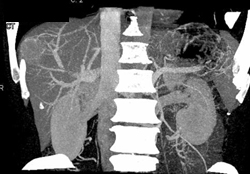

Extreme Gastric Varices